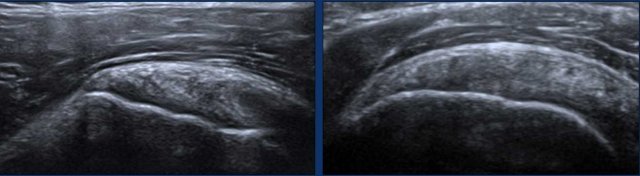

Anisotropy of the LHB Anisotropy of the LHB

Anisotropy

Anisotropy is an artifact that occurs when the ultrasound beam is not perpendicular to the LHB tendon. This misalignment leads to reduced sound wave reflection, resulting in a loss of resolution and a darkened, hypoechoic appearance of the structure (black arrow). In some cases, this may give the impression that the LHB tendon is dislocated from the intertubercular groove.

To correct for anisotropy, reposition the transducer so that the ultrasound beam is perpendicular to the tendon. The LHB will then regain its typical echogenic, fibrillary appearance (white arrow).

It is important to note that anisotropy can also affect other structures, such as the subscapularis tendon in this image, which similarly appears anechoic due to this artifact.